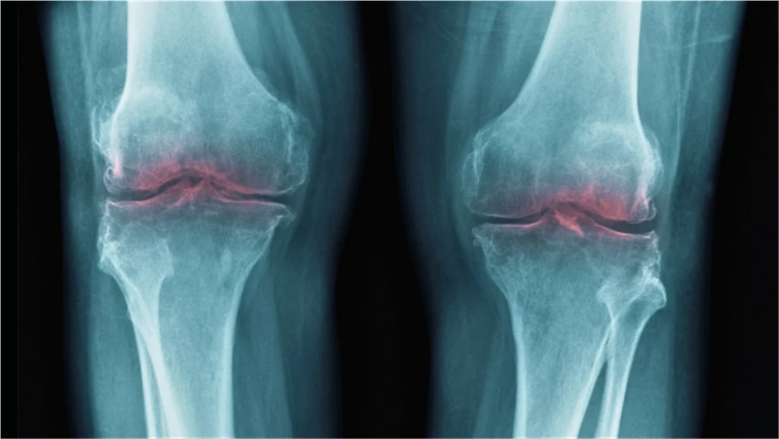

صدمة علمية إيجابية، هكذا يمكن وصف الاكتشاف الجديد الذي يبشر بأمل كبير لملايين البشر حول العالم. كشفت دراسة حديثة عن مفتاح سحري محتمل لتجديد الغضروف وعلاج آلام المفاصل المزعجة، وهي مشكلة يعاني منها بالأساس كبار السن، وتؤثر على جودة حياتهم بشكل كبير.

تشير هذه الدراسة إلى أن فقدان الغضروف المرتبط بالشيخوخة ليس مجرد عملية طبيعية لا مفر منها، بل يرتبط ببروتين واحد محدد، الأمر الذي يفتح الباب أمام علاجات مبتكرة قد تعيد الحركة وتخفف بشكل كبير من الانزعاج والألم الذي يشعر به الكثيرون.

جاء هذا الاكتشاف المذهل من خلال دراسة علمية أجريت على مجموعة من الفئران، حيث تبين أن بروتينًا معينًا، يُسمى 15-PGDH، يزداد وجوده بشكل ملحوظ مع التقدم في العمر. هذا البروتين لا يعمل بمفرده، بل يتداخل سلبًا مع الجزيئات التي تلعب دورًا حيويًا في عملية إصلاح الأنسجة وتقليل الالتهابات داخل الجسم.

شملت التجارب العلمية التي أجريت في جامعة ستانفورد، فئرانًا مسنة كانت تعاني بالفعل من تآكل في غضروف الركبة. بعد تطبيق مثبط خاص لإنزيم بروتين 15-PGDH، لاحظوا زيادة في سُمك هذا الغضروف المتآكل، وهو ما يعد مؤشرًا إيجابيًا للغاية على قدرة هذا المثبط على تجديد الغضروف.